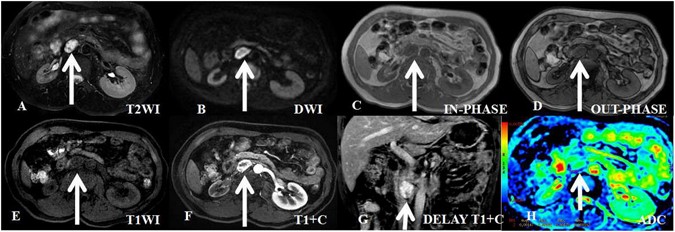

A 49-year-old asymptomatic man with incidentaloma and a histologically proven benign retroperitoneal paraganglioma at the right prevertebral region (between the inferior vena cava and aorta). The transverse and longitudinal diameters of the tumor are 2.61 cm and 3.13 cm, respectively. (A) in axial T2-weighted imaging, the tumor demonstrates high signal intensity and isointensity compared with the gluteal muscles. The intratumoral cystic areas exhibit higher signal intensity. (B) In axial DWI, the tumor exhibits ring-shaped high signal intensity. (C–E) T1-weighted imaging (in-phase, out-phase and pre-scanned imaging, respectively); the signal of the tumor is slightly lower than that of the gluteal muscle. (F) In contrast T1-weighted imaging during the arterial phase, the tumor is clearly enhanced and non-homogeneous. (G) In coronal T1-weighted imaging during the delay phase, the tumor is clearly enhanced and non-homogeneous. (H) ADC imaging; the mean ADC value of the ROI of the tumor is 0.00147 mm2/s.